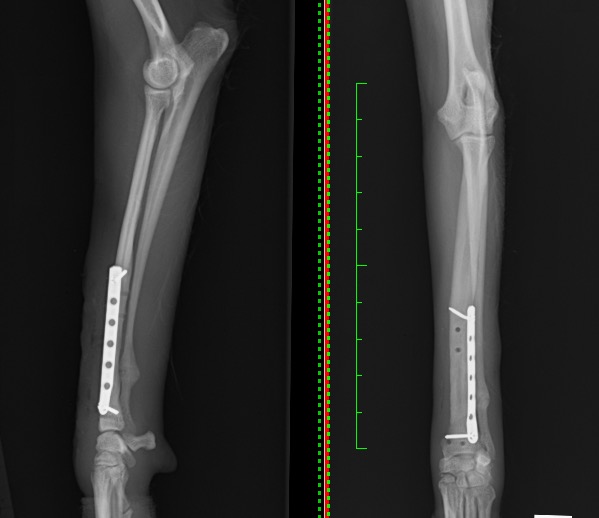

1、2枚目は前腕部(手根~肘)の骨(橈骨・尺骨)のX線写真になります。

1枚目が正面から撮影したX線写真、2枚目が横から撮影したX線写真です。赤矢印が骨折部位になります。

この子は左前肢の橈骨尺骨骨折でしたが、骨折していない右前肢を同条件下で撮影し比較することにより、

より異常所見が検出しやすくなります。

正面に1.5mmのT字プレート、外側面に1.3mmのストレートプレートを設置するダブルプレート法による整復を行いました。

左が側面像、右が正面像になります。

整復後 Lateral/AP